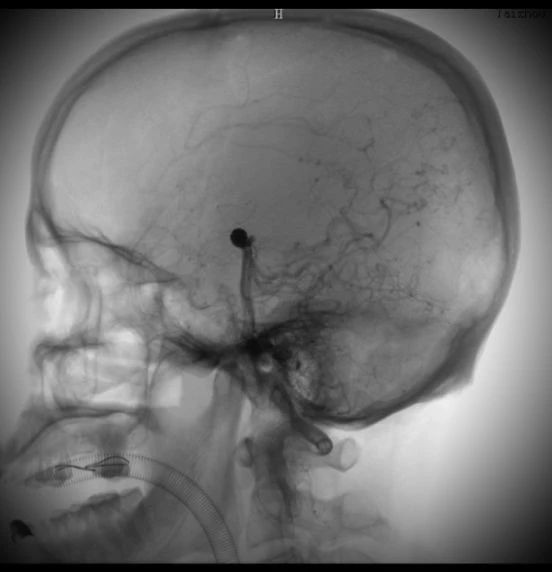

動脈瘤在這里↓↓↓

術(shù)中造影顯示的顱內(nèi)動脈瘤,大家不要小看它,它要是破裂了,可是會要人命的。所以顱內(nèi)動脈瘤又稱為腦子里的定時炸彈。

術(shù)后的動脈瘤長這樣。因為動脈瘤里填充了彈簧圈,所以在X線照射下整體看起來是黑色的